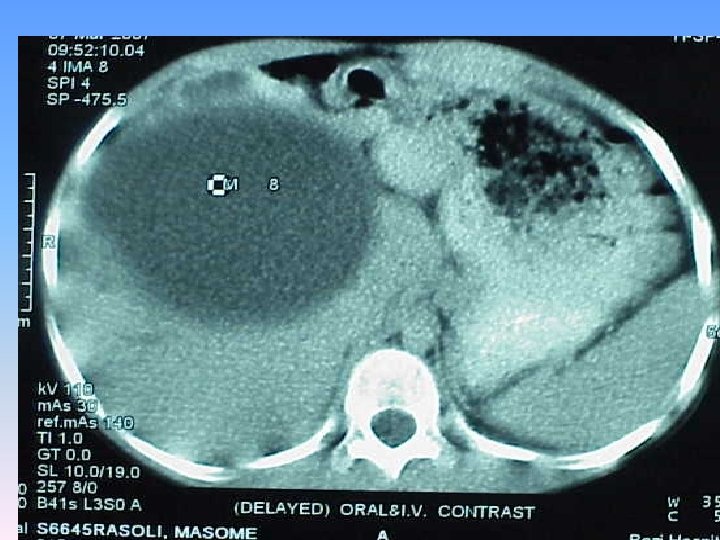

Abdominal CT Scan § A regular lobulated cystic mass in right lobe of liver (120 x 120) without calcification causing dilatation of intra & extra biliary ducts.

MRCP & MRI § Huge thicked wall cystic mass (140 x 120 mm), at the portahepatis that seems connected to biliary tree and gall bladder, resulted in severe dilatation of intra hepatic bile ducts and displaced right kidney posteriorly. § Spleen, kidneys, bowel loops and abdominal wall are normal. § Finding could be due to congenital anomalies like choledocal cyst, Duplication cyst, mesenteric cyst and hydatid cyst are in DDx.

Surgery report § There was a mass(10 x 20 cm) in hilum of liver which had compressed the duodenum anteroinferiorly. It was not resectable because of extension and adhesion to the mesocolon & stomach. § Gall bladder was bilobulated. § Stomach , intestine & uterus were normal. § Cyst was draineged which was full of bile. § Cystodoudenostomy to D 2 was done.